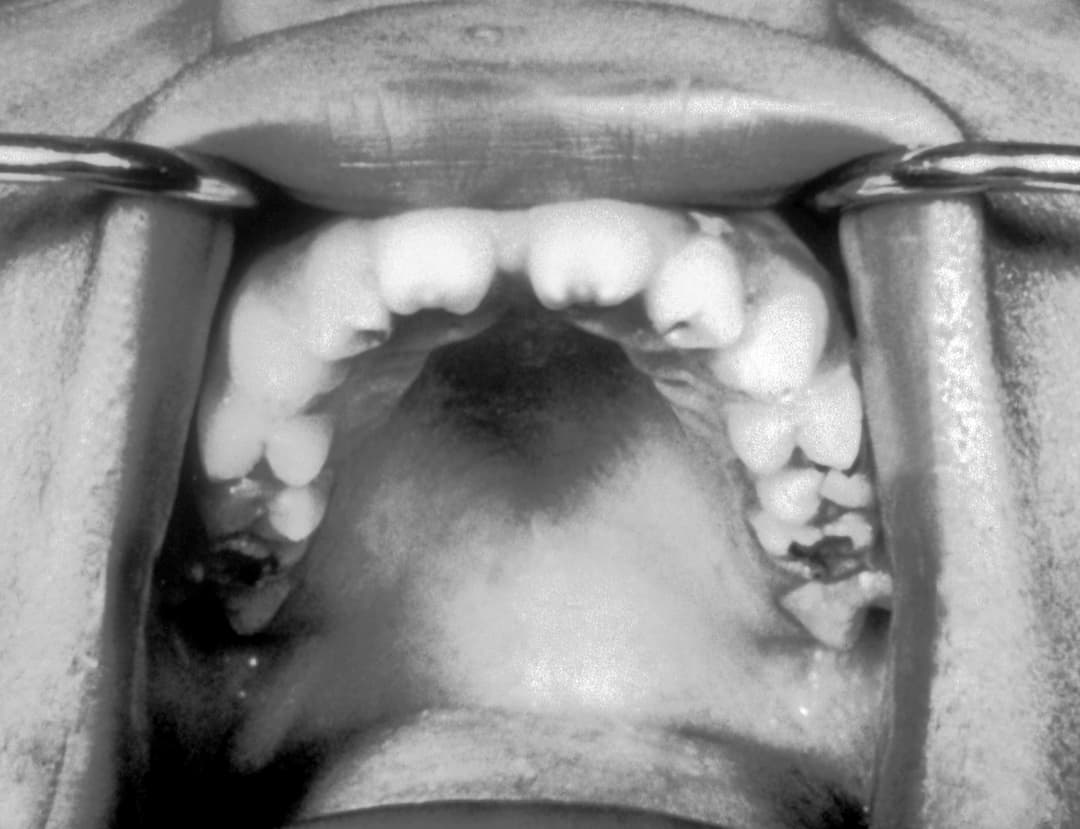

السفلس الولادي: الأسباب والأعراض والتشخيص والعلاج